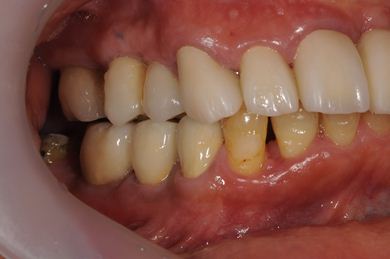

インプラントの症例写真 IMPLANT

骨再生インプラント治療

| 治療方針 | 右上奥はソケットリフトにて上顎洞拳上してインプラント埋入を可能にし、上顎前歯部は骨再生法によりインプラント治療を行う。その他、補綴により口腔内全体の機能的審美的回復を行う。 | ||||||||||||||||||||||||||||||||

| 治療内容 | インプラント8本(GBR、ソケットリフト)、ハイブリッドセラミッククラウン17本(セラミック用土台5本) | ||||||||||||||||||||||||||||||||